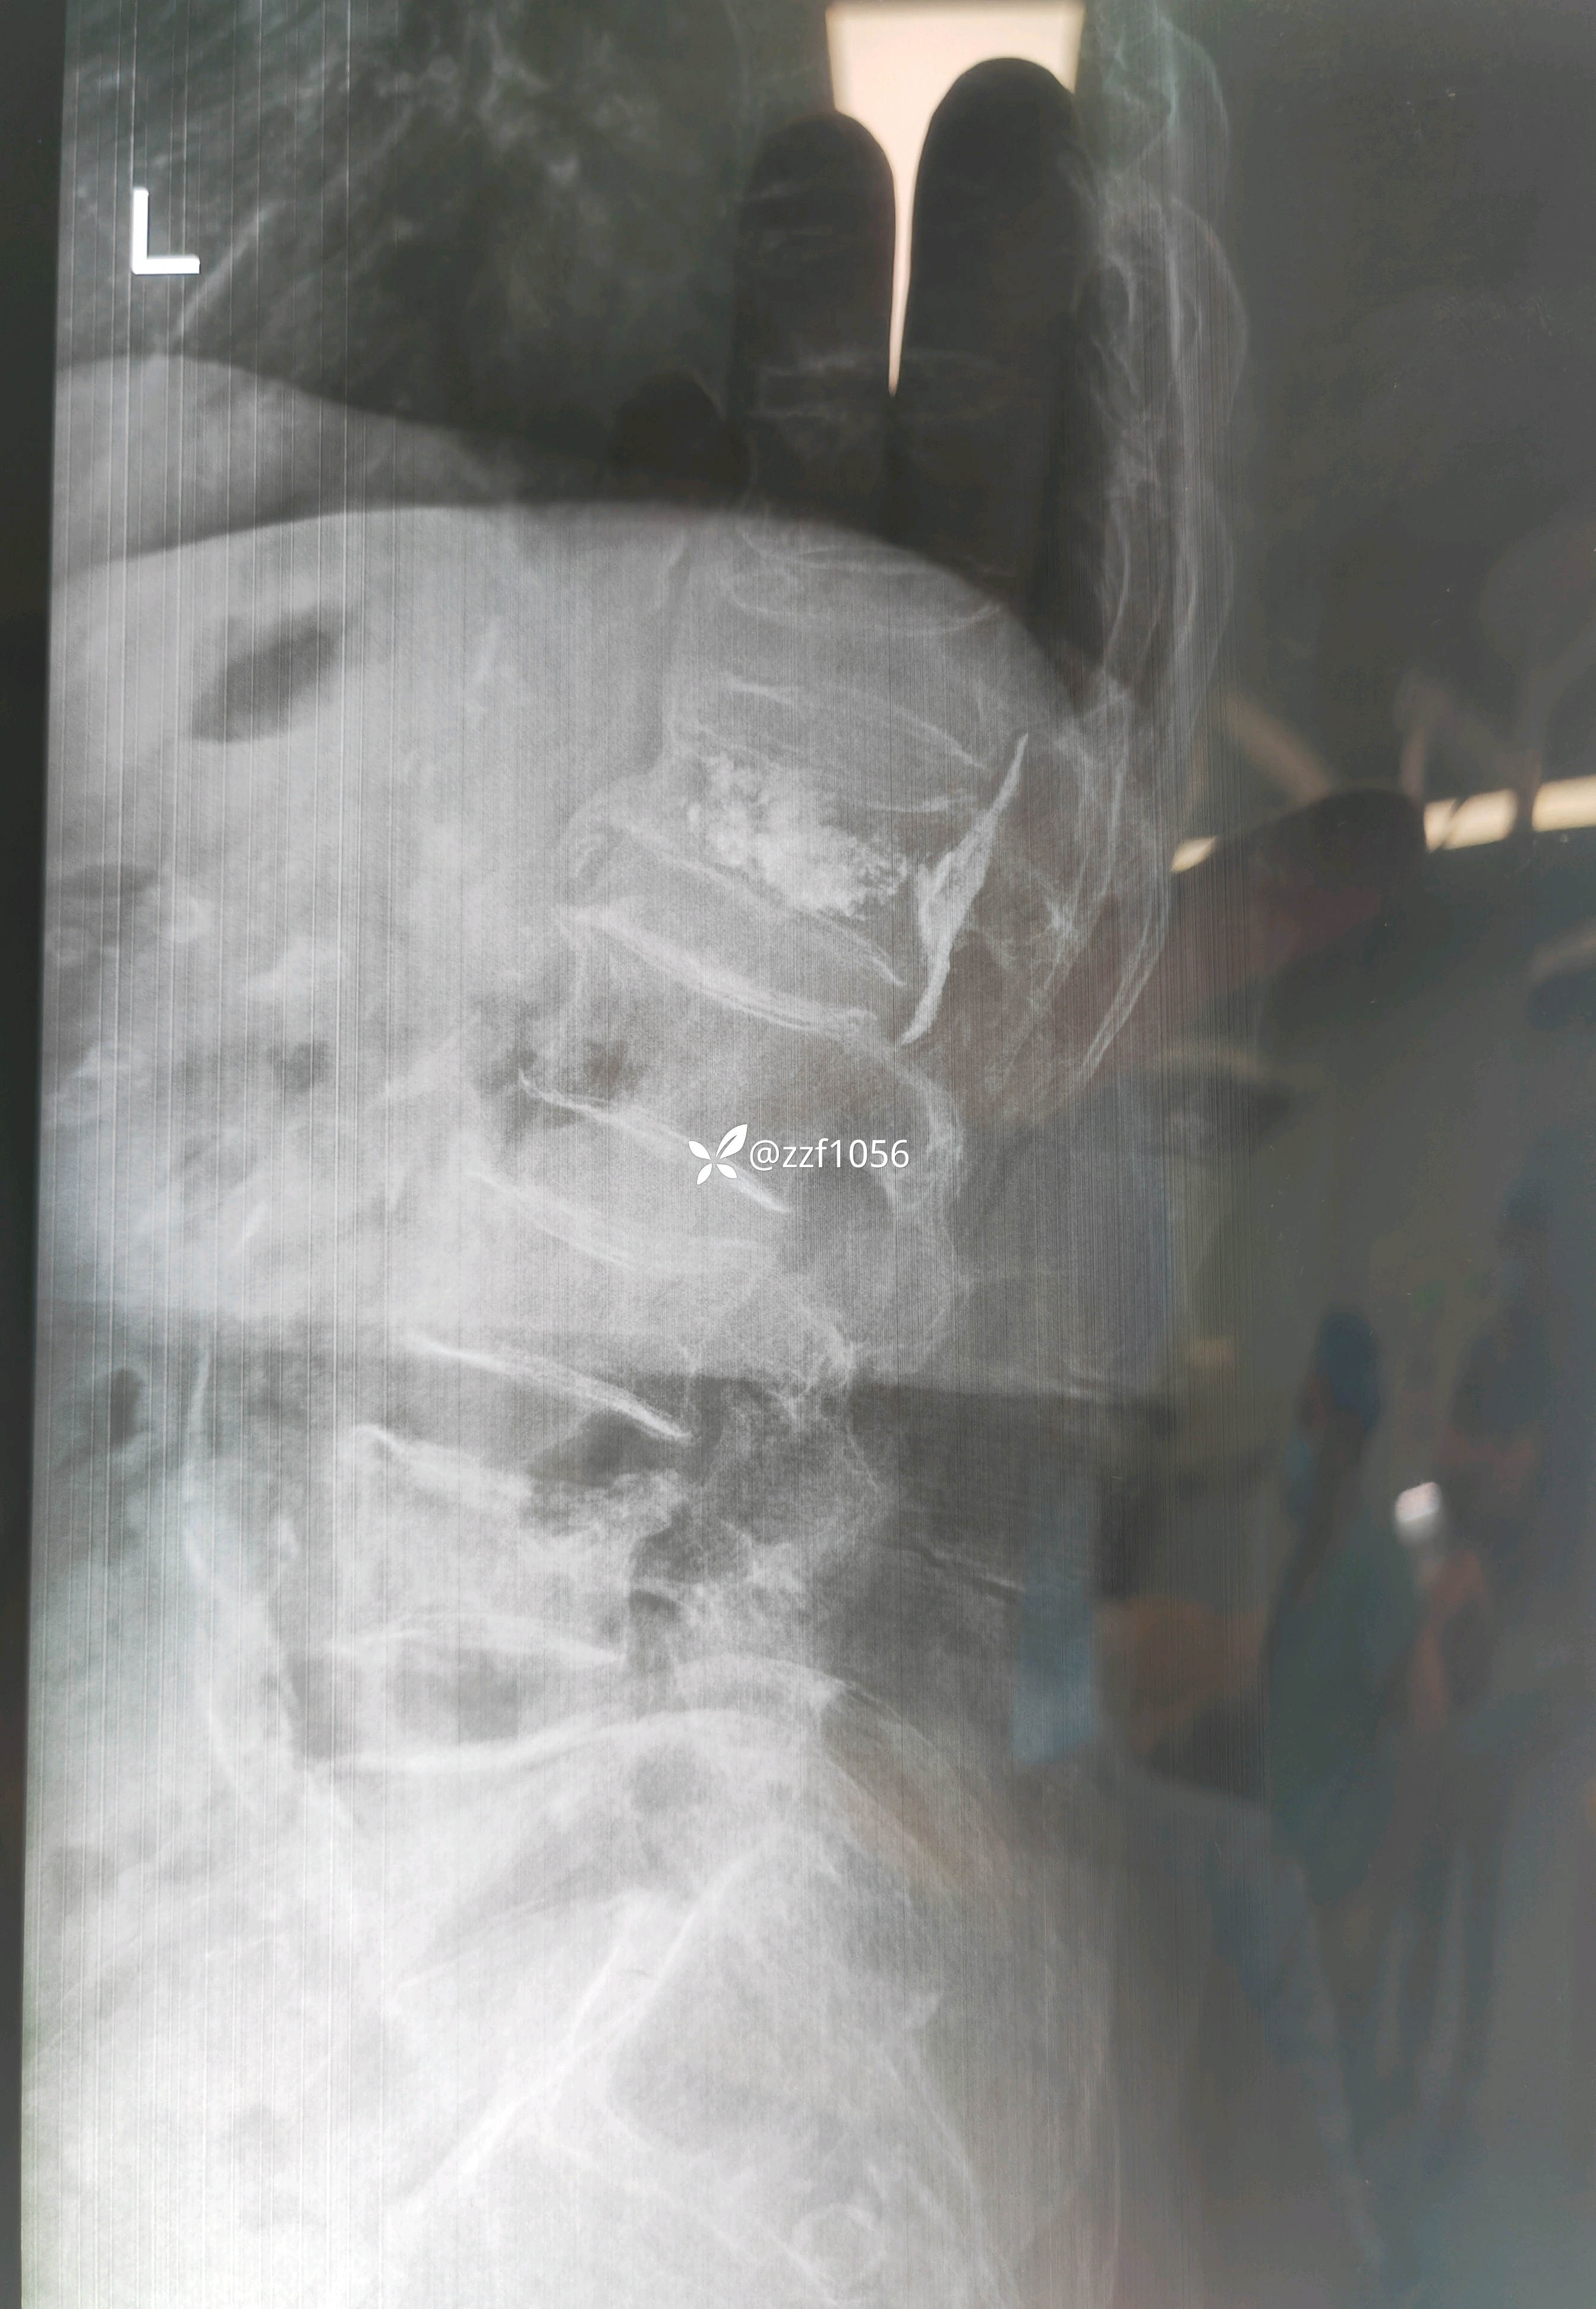

仔细一看这个侧位片,吓我一跳,骨水泥进椎管了?

家属自诉一年前患者腰1压缩骨折,在外省地医院行椎体成形术,术后恢复良好,日常正常行走。